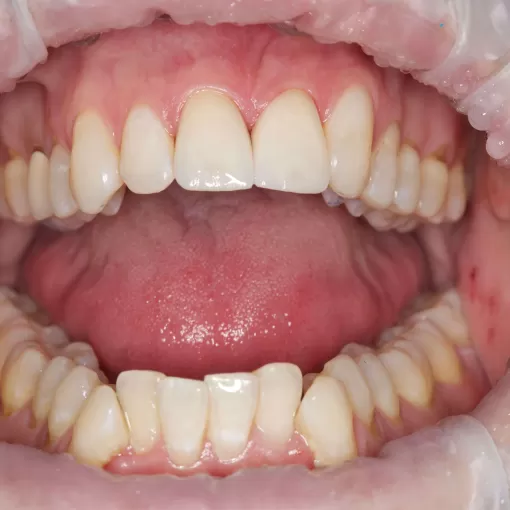

Пациентке было установлено два импланта и через 4 месяца выполнено протезирование циркониевыми коронками на имплантах с использованием индивидуальных абатментов в области зубов 1.2 и 1.1 и коронкой E-max на зуб 2.1.